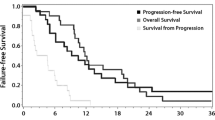

The onset of imaging changes ranged from 1 month in cases of white matter changes and pseudoprogression to 65 months in a case of pseudoprogression and radiation-induced arteriopathy.

The duration of changes ranged from 1 to 61 months. In the cases of arteriopathy and parenchymal atrophy, the changes were irreversible. In the remaining two categories, there were some instances of transient change, as per the definition of the categories. The chronological parameters for these categories are as shown in the below bar diagrams (Figs. 7 and 8).

There was no clear relationship between imaging change type, tumor type, and imaging change chronology.